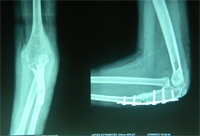

Treatment Options

The main aim of the operation is to achieve a stable radial head reduction without significant loss of joint motion

Open reduction of the radio-capitellar joint with ulnar angulation osteotomy. The ulnar—distraction osteotomy to achieve radial head reduction. No ligament reconstruction was required. Monteigga Fracture – Dislocation.